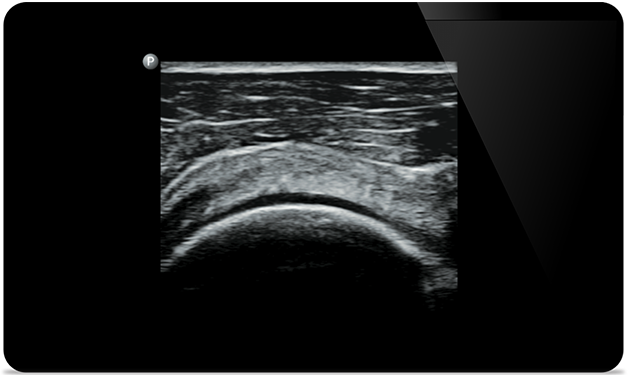

Lumify помогает визуализировать мелкие детали мышц, суставов, связок, сухожилий и хрящей, чтобы поставить более точный диагноз при травмах.

Lumify поможет вам обследовать пациента с головы до ног независимо от диагноза, будь то плантарный фасциит, тендинит или бурсит надколенника или даже нестабильность вращательной манжеты плеча.

SonoCT улучшает визуализацию настоящих тканей, устраняя случайные артефакты. Эта технология позволяет получать изображения, превосходящие по качеству обычные изображения, у 94% пациентов.

Расширенный диапазон рабочих частот — от 5 до 2 МГц. • Радиус кривизны 50 мм. - 2D, цветной доплеровский режим, М-режим, продвинутая визуализация XRES и многомерная гармоническая визуализация, SonoCT. • Визуализация с высоким разрешением для исследований глубоко расположенных структур: оптимизированные предустановки для исследований брюшной полости, желчного пузыря, легких и для диагностики в акушерстве/гинекологии.